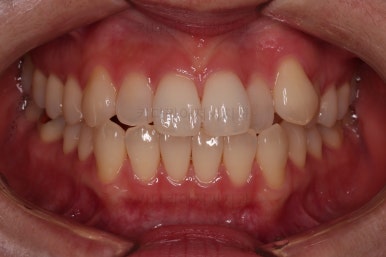

4. 마무리

철사교정과 마찬가지로 앞니쪽에 유지장치를 구성하고 치료를 종료합니다.

매우 가지런해졌고요.

맞물림도 좋아졌고, 중앙선도 잘 맞춰졌습니다.

부산인비절라인 전후 비교해 보겠습니다.

입매를 유지하면서 비발치이더라도 입이 더 나오지 않게 마무리 했고요.

가지런한 느낌 좋고, 중앙선이라던지 교합도 좋아졌습니다.